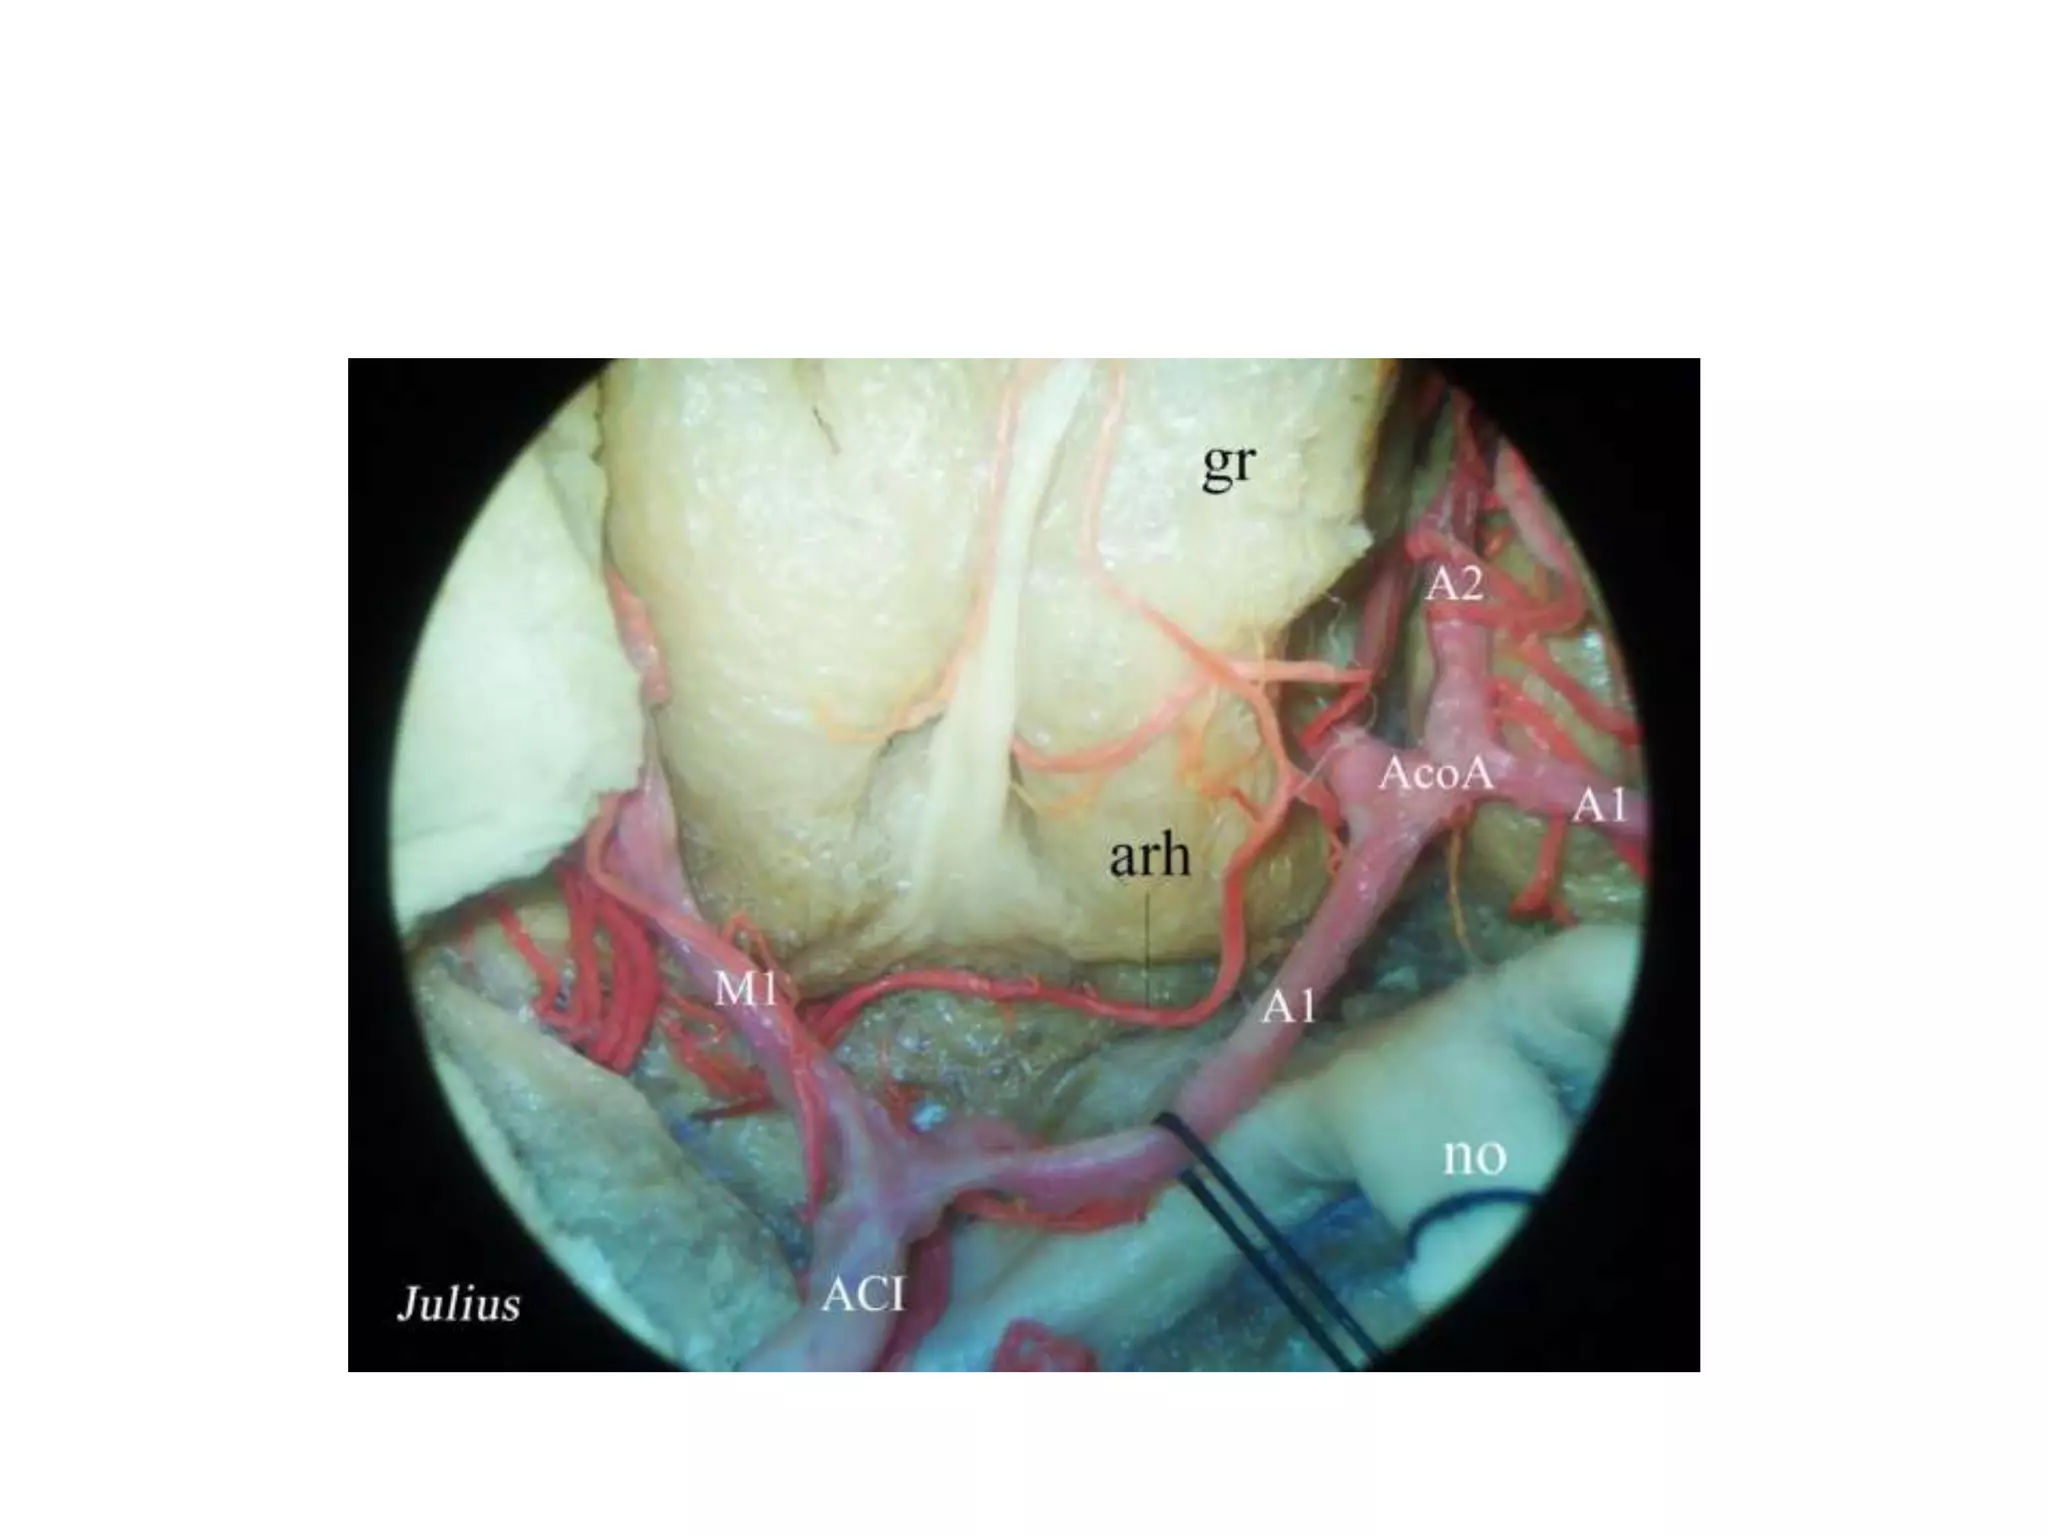

ACA

The recurrent artery of Heubner usually origins from the post-communicating segment of the anterior

cerebral artery (ACA). It doubles back the ACA to reach the medial part of the Sylvian fi ssure, below

the anterior perforated substance. Sometimes its path is so long that the artery loops below the basal

surface of the frontal lobes. Not frequently more than one recurrent arteries can be present (Rhoton

2003 ). According to Lang the artery is double in about 30% of cases (Lang 1995 ) .

Recurrent artery of heubner originates

near Acom

(A) The middle cerebral artery (MCA) gives rise to the lateral lenticulostriate arteries

(LLA) at the bifurcation complex. The medial lenticulostriate arteries (MLA) arise from

the proximal section of A1. At the juncture of A1-AComm-A2 the recurrent artery of

Heubner (RAH) is given off. AComm completes the anterior portion of the circle of

Willis and has several perforating vessels ( Acomm Perf) that head posteriorly. In the

first 5 mm of A2 the orbitofrontal ( OF) artery is given off with the frontopolar (FP)

artery staying more medial. (B) A clinical picture after removal of a tuberculum sella

meningioma with a well-defined display of the anterior cerebral arteries.

Recurrent artery of heubner [ R-RAH ]

originates near Acom